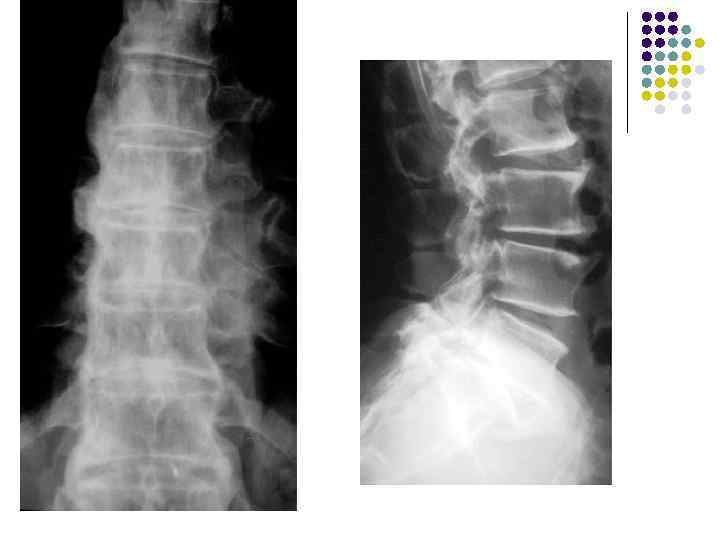

Болезнь Форестье (фиксирующий гиперостоз) 1. Чаще поражается грудной отдел с дальнейшим распространением на шейный и поясничный 2. Происходит костеобразование под передней продольной связкой толщиной до 1 -1, 5 см 3. Тела позвонков утолщены из-за периостальных наслоений 4. Высота межпозвоночных дисков не изменена 5. Дугоотросчатые крестцово-подвздошные, реберно-позвоночные суставы не страдают. На начальном этапе спондилёз и болезнь Форестье не различимы

Болезнь Форестье

l На рентгенограмме грудного отдела позвоночного столба в боковой проекции определяются признаки выраженных, распространенных дистрофических изменений в виде болезни Форестье за счет характерных костных разрастаний под передней продольной связкой практически во всех визуализированных отделах грудной части позвоночника. На этом фоне отмечаются также явления умеренного и также распространенного отсеохондроза – сужение межпозвонковых простанств, субхондральный остеосклероз, соответствующие костные разрастания. Положение тел позвонков правильное, деструктивных изменений нет.